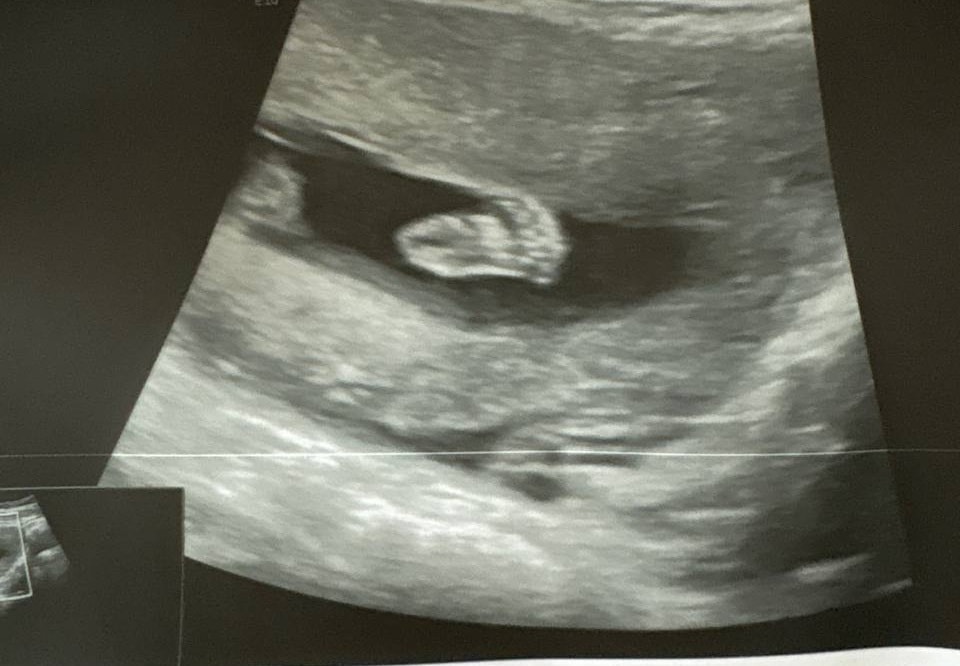

Одуванчик, Изображение

Яна, получается, тоже часть ручки между кулачком и телом не видно. Значит, да, ткани пропускают волны сквозь себя. Скорей всего на фото в посте тоже и руки и ноги вверх задраны, просто их волны не отразили, потому что ребенок не мог их задрать так, чтоб они вдоль тела легли

Одуванчик, это рука, которая как бы дальняя, левая и колено видно, а та что ближе, ее не видно. Волны проходят глубже. Как бы ребенок в разрезе получается😄